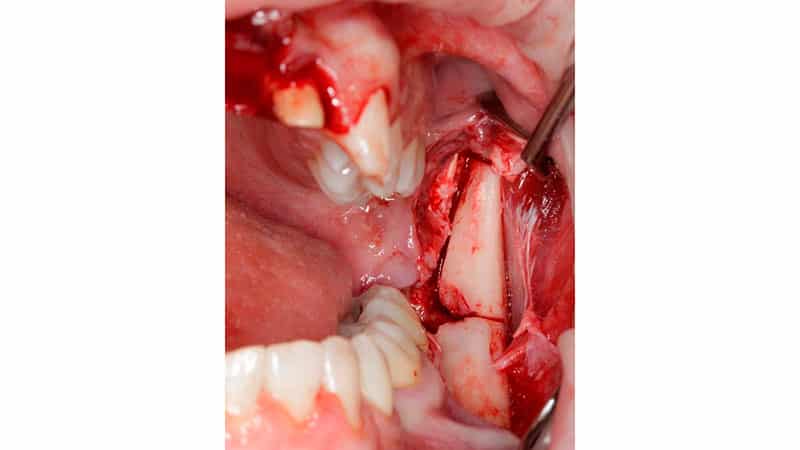

Лечению указанные выше проблемы не поддаются. Удаление дистопированных и ретинированных зубов мудрости представляет собой сложную задачу и может вызывать значительную боль, так как такие зубы не полностью прорезаются из челюсти и иногда даже не выходят через десну. Операции по их удалению проводятся только под действием обезболивающих средств, и врач начинает манипуляции лишь после того, как анестезия подействует на пациента.

Для удаления такого зуба специалист делает надрезы в слизистой оболочке и сверлит отверстие в кости нужного диаметра. Если зуб слишком большой, его предварительно разбивают на несколько частей, что облегчает процесс извлечения. После завершения операции в челюсти остается пустота. Для ускорения заживления, предотвращения инфекции и уменьшения болевых ощущений в образовавшуюся полость вводят лекарственные препараты. В некоторых случаях большой надрез может потребовать зашивания.